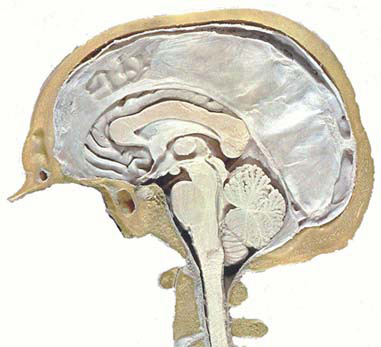

Une coupe mdio-sagittale de la fosse

postrieure montre lÕaspect grossirement triangulaire de la loge occupe par

le cervelet. Cet espace est dlimit par: le ple occipital en haut, le tronc

crbral en avant et lÕcaille occipitale en bas.

Imag. 01 - Coupe mdio-sagittale du crne (Atlas Sandoz)

Imag. 02 - Coupe mdio-sagittale de lÕencphale (CHU Rabat) |

Ces limits correspondent aux trois faces du

cervelet : une face antrieure ou ventrale (c) rattache au tronc crbral

(tc), et deux faces dorsales, dlimite par une crte, la face suprieure (a)

moule contre la tente dure-mrienne qui la spare du cerveau, et la face

infrieure (b) applique contre le squelette occipital.